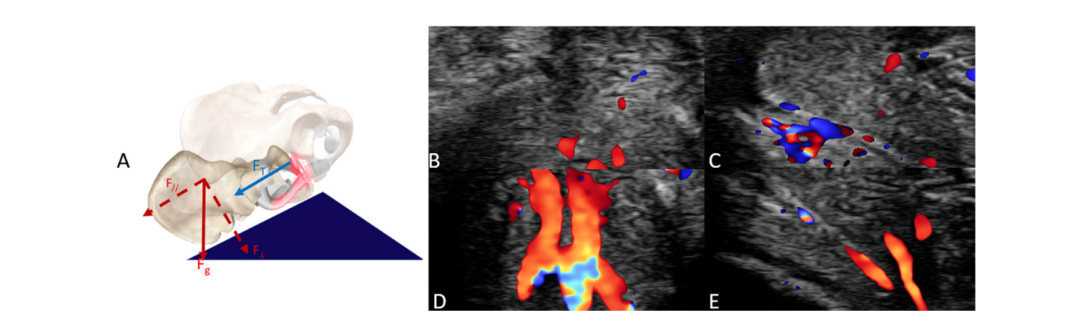

在面对面-男上位的姿势下,使用枕头和不使用枕头对比:效果有明显差异!

▲面对面-男上位使用枕头

垫枕头不仅能优化伴侣之间的接触角度,让身体更贴合,还能通过改变受力点增加摩擦和深度,更容易刺激到敏感点。

更巧妙的是,由枕头形成的“斜面”还会改变力的方向,使得力量更有效地指向女性Y蒂,对接触、压力和深度的优化,能让Y蒂获得更均匀、更强烈的受力,使血流增加更集中。